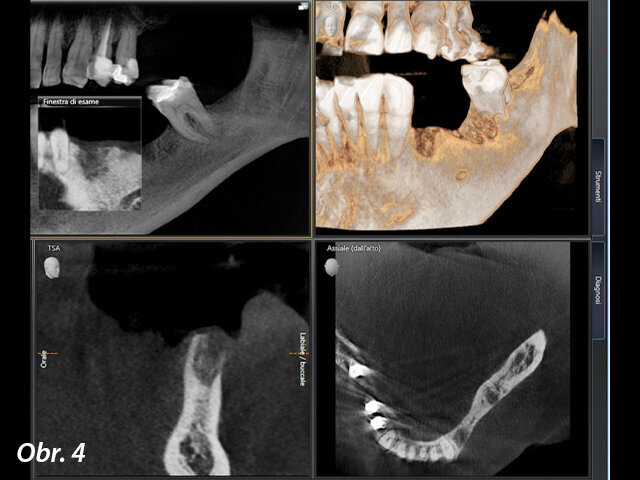

V místech zubů 34 a 36 byla naplánována fixní náhrada nesená implantáty. Z tohoto důvodu bylo provedeno vyšetření pomocí CBCT, které mělo pomoci posoudit kvalitu a kvantitu kosti pro zavedení implantátu (obr. 4, 5). Byl shledán dostatek vertikální kosti v obou místech, nicméně v oblasti zubu 34 bylo pro zavedení implantátu nedostatečné horizontální množství kosti. V této lokalitě byla tedy spolu se zavedením implantátu naplánována augmentace kosti pomocí xenoštěpu a kolagenní membrány a keramický vhojovací abutment.